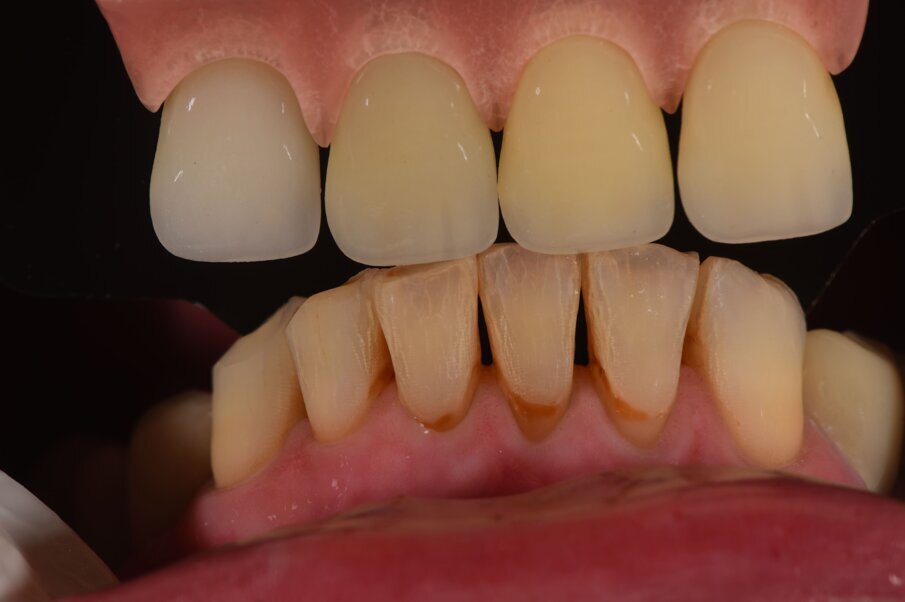

I dati raccolti sono molti ma la procedura digitale consente di sommarli e confrontarli senza limiti e indicando le possibili migliori e correzioni lungo il percorso. Dopo un breve periodo di condizionamento dei tessuti (Fig. 30) rileviamo l’impronta master per la finalizzazione ultima della riabilitazione protesica. L’impronta degli elementi naturali viene rilevata posizionando dei fili detrattori secondo la tecnica del doppio filo mentre per gli impianti verranno usati gli scan body dedicati (Fig. 31). Le potenzialità digitali consentiranno di avere una stabile lettura della posizione di centrica rilevandola prima della rimozione dei provvisori e sovrapponendola a provvisori rimossi (Fig. 32). In laboratorio l’odontotecnico realizza i modelli (Figg. 33, 34) sovrappone le immagini (Fig. 35) e raccoglie gli elaborati dei vari passaggi che porteranno alla finalizzazione del progetto digitale (Figg. 36, 37). Gli impianti in Zirconia non offrono molte soluzioni protesiche, è importante che il loro posizionamento tenga conto di quest’aspetto mettendo l’odontotecnico nelle condizioni più favorevoli (Fig. 38). Questa sistematica prevede l’uso di un moncone in titanio cementato nella struttura protesica che permette l’avvitamento all’interno dell’impianto. Nella connessione implantare è presente un’intercapedine dove alloggia il collarino in titanio del T-base totalmente inglobato all’interno della zirconia, evitando comunicazioni coi tessuti adiacenti. Va comunque considerato l’aspetto tecnico importante legato allo spessore della struttura in zirconia che deve avvolgere l’intero moncone in titanio. (Fig. 39, 40).

Fig. 35_Sovrapposizione di un’immagine stilizzata degli elementi realizzabili con un margine muso ricreato.

Fig. 36_Wax-up digitale funzionalizzato per entrambe le arcate in visione frontale.

Fig. 37_La medesima immagine viene sottratta dagli elementi di supporto. Tale visione consente di evidenziare i margini coronali, di valutare i movimenti masticatori, gli svincoli coronali le conformazioni anatomiche ottimizzando le singole funzioni.